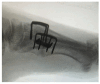

Background: Continuous Compression Implants (CCIs) are low-profile implants made of nitinol and titanium. They offer multiple benefits in comparison to plate and screw fixation for foot and ankle indications, and they are designed in such a way that they continuously and dynamically compress the opposed bony surfaces throughout the entire healing process. Methods: In this study, we present our experience on the use of those nitinol implants for midfoot and hindfoot surgery. Furthermore, we elaborate on the advantages and downsides of using this internal fixation method and highlight common pitfalls which could lead to undesirable clinical outcomes. We also demonstrate our proposed surgical technique on how to use CCIs in a reproducible and reliable way and present surgical tips which could help reduce surgical time when utilising these implants. We also make surgical recommendations on their use and present the underlying biomechanics, which could provide a better understanding of the rationale behind using them in the field of foot and ankle surgery. Last but not least, we presented the early clinical and radiological results of a series of patients who underwent primary midfoot fusion for Lisfranc injury between 2020 and 2023. Results: With a minimum follow-up of 9 months, satisfactory clinical and radiological union was noted in all those patients. The mean difference between pre- and post-operative MOxFQ scores was -37.7 (95% CI was 16.9 to 58.5; p = 0.03). The mean post-operative VAS pain at rest was 3.2 (SD = 2.3). No major complications were noted. Conclusions: CCI internal fixation is a safe, reproducible, and reliable method when it comes to foot and ankle conditions, but it requires appropriate pre-operative planning, surgical training, and careful implantation.